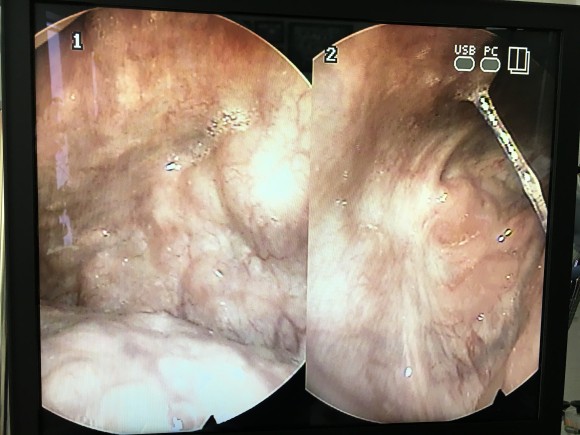

상단:편도와의 윗부분에 결석이 끼여있는 모습과 제거한 편도 결석, 하단:고주파 시술과 PITA 시술 일주일과 3주차의 모습